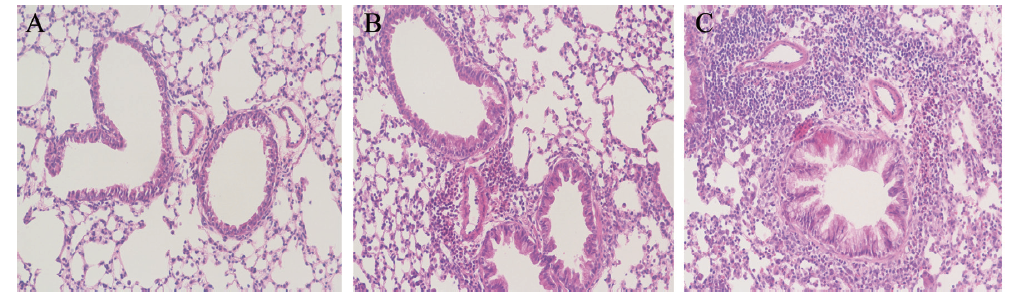

相对于空白对照组和致敏组而言,哮喘模型组中的支气管及伴行的血管周围有大量炎症细胞浸润,以嗜酸性粒细胞和淋巴细胞为主,且支气管的管壁增厚、上皮细胞损伤,表明该小鼠哮喘模型建立成功,见图1

图1 空白对照组、致敏组和哮喘模型组小鼠的肺组织病理结果(HE染色,×200)

A:空白对照组;B:致敏组;C:哮喘模型组